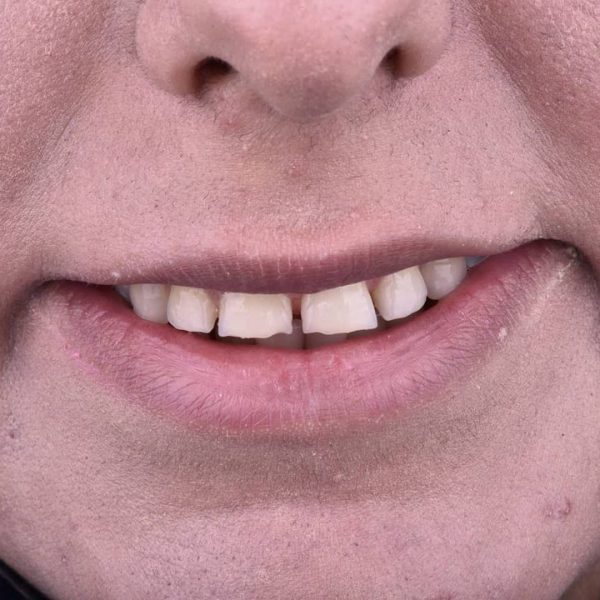

درمان: کامپوزیت ونیر دندانهای قدامی جهت بستن فواصل بین دندانی و بهبود رنگ دندانها به خواست بیمار.